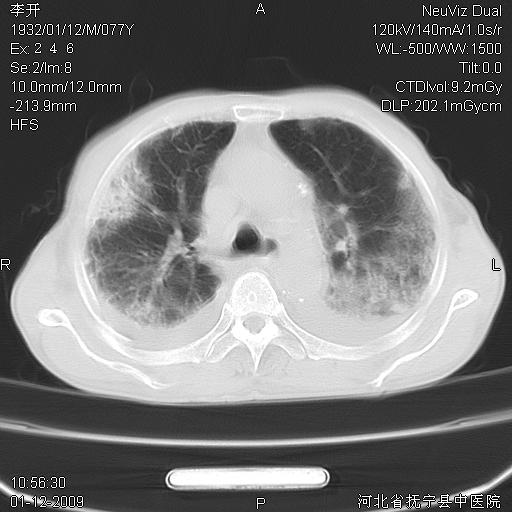

以下是引用黑白光影在2009-1-19 16:49:00的发言:[br]心衰肺水肿;心包、胸腔积液;冠脉钙化;肺部感染。